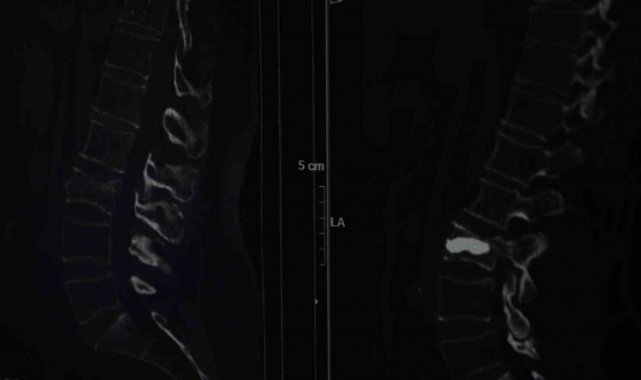

İstanbul'un Sarıyer ilçesinde Kilyos'taki evinde tek başına yaşayan 2 çocuk annesi emekli mali müşavir olan 76 yaşındaki Alis Armağan, iddiaya göre ağustos ayında evinin bahçe kapısının önünde düştü. Düşme sonrası omurganın bel bölgesinde kırık meydana geldi ancak Armağan ağrılarını bel fıtığına bağladı. Bir süre bu şekilde düşünen Armağan, ağrıları geçmeyince Şişli Hamidiye Etfal Eğitim ve Araştırma Hastanesi'ne başvurdu. Burada Beyin ve Sinir Cerrahisi Uzmanı Doç. Dr. Şevket Evran ve ekibinin yaptığı incelemelerde kemik erimesine bağlı kırık tespit edildi. Armağan, durumu şaşkınlıkla karşılarken doktorlar operasyon gerekliliğini ifade etti. Genellikle kemik erimesine bağlı omurga kırıklarını tedavi etmek amacıyla uygulanan minimal invaziv bir cerrahi yöntem olan ve hastanın aynı gün normal yaşamına dönebilme imkanı sunan kifoplasti operasyonu 25 Ağustos günü gerçekleştirildi. Doç. Dr. Evran ve ekibinin yaptığı operasyon başarılı geçerken Armağan da rahat bir nefes aldı. Doç. Dr. Evran, özellikle menopoz sonrası kadınlarda kemik erimesi kaynaklı oluşan kırıklarına dikkat çekerken tedavilerine ilişkin bilgi verdi, vatandaşlara önemli uyarılarda bulundu.

"Omurga kırıklarını menopoz sonrası bayanlarda sıklıkla görüyoruz" diyerek sözlerine başlayan Doç. Dr. Evran, "Bu hastalarda travma sonrası kemik yoğunlukları düşük olduğu için omurgalarında kırık oluşma ihtimali normal popülasyona göre çok daha fazla görülüyor. Travma geçiren menopoz sonrası bir insanda kemik yoğunluğuna daha önce dikkat etmemiş, bununla ilgili daha önce tedavi almamışsa bu hastalarda travma sonrası oluşan, bel, sırt, boyun ağrılarında özellikle bu kırıklar düşünülmekte. Bir beyin ve sinir cerrahisi hekimine başvurmaları önerilmekte. Vücudun daha çok yük taşıyan bel ve sırt bölgelerinde oluşuyor. Hasta sırt veya bel ağrısıyla travma sonrası başvurduğu zaman önce gerekli tetkiklerini yapıyoruz. Görüntülemelerinde kırığı tespit etmiş olursak ve bu bir travma sonrası gelişen bir kırıksa bu kırıkta öncelikle omurgadaki çökme miktarının derecelerine bakıyoruz. Derecelere göre korse, yatak istirahati gibi tedavileri öncelikle deniyoruz. Fakat kırığın çökme derecesi çok ileriyse veya omuriliğe bir zarar söz konuysa daha minimal invaziv olarak tedaviler ve daha ileri hastalarda cerrahilerle omurgaya enstrümantasyonlarla tedavi edebiliyoruz" dedi.

Tedavi seçeneklerine yönelik konuşan Doç. Dr. Evran, "Hastanın klinik durumu uygunsa vertebroplasti veya kifoplasti dediğimiz halk arasında omurgaya çimento doldurma olarak bilinen işlemi bu hasta grubunda uygulamak öncelikli tercihimiz oluyor. İşlemin bazı avantajları var; eskiden bu tarz kırıklarda hastaları günlerce yatakta yatırıp hatta tüm vücut alçıya alınıp tedavi edilirmiş ama günümüzde teknolojinin de ilerlemesiyle artık bu yöntemler daha ön planda. Vertebroplastide hastanın cildinde büyük bir kesi olmadan sadece bir iğnenin geçtiği kadar bir delikten iğne yardımıyla girilerek omurganın içine bazen tek bazen çift taraflı girilerek başlangıçta içinde sıvı olan sonra katılaşan bir maddeyi enjekte ediyoruz. Omuriliğin içinde donuyor. Başka bir yöntemi olarak da bazen omurganın içinde bir balon yardımıyla balon şişirerek omurganın eski yüksekliğini kazanmasına ve daha güvenli bir alan oluşturarak balonun şiştiği alana çimento dediğimiz şeyle doldurarak hastanın da ağrılarının geçmesini sağlamış oluyoruz, akşamına hasta taburcu edilebiliyor" diye konuştu.

Sözlerini sürdüren Doç. Dr. Evran, "Bu tarz hastalar kliniğimize çok başvuruyor sadece kliniğimize değil Türkiye hatta dünya genelinde bu tarz hastalar çok fazla. Bu cerrahiyi uyguladığımız ayda ortalama 4 ila 5 hasta. Bu hastamızda bir travma sonrası bel omurgasında kırık meydana gelmiş, ilk planda kırık olarak algılamıyor, şiddetli ağrılardan vücudunda kötü bir şey geliştiği yönünde bir kanaate varmış. Ameliyat sonrası 4'üncü saat, ayağa kalkarak yürümesini sağladık. Osteoporoz olan hastalarda omurga kırıklarını önlemenin yollarından bir tanesi de menopoz sonrası bayanların mutlaka kemik yoğunluğuna baktırması gerekiyor. Hastalar bu tarz travmalardan sonra ağrılarını birçok şeye yorabiliyor. Özellikle bel fıtığı, belinde kas güçsüzlüğü, düzleşme gibi hastamız da önce bel fıtığından şüphelenerek ağrılarının ona bağlı olduğunu düşünmüş fakat dirençli bir ağrı. Hiçbir medikal tedavi, ilaçla ağrıları dinmeyince durumun daha farklı boyutta olduğunu düşününce hastanemize başvurmuş" dedi.